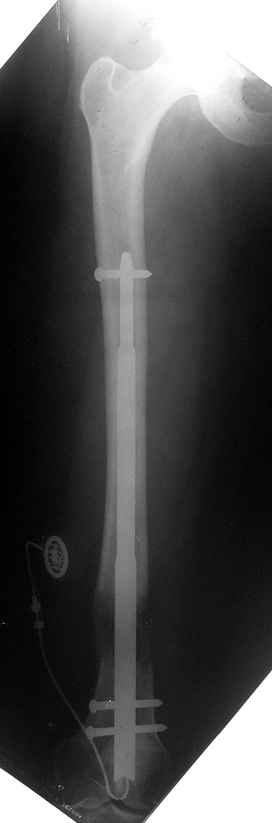

Case 1